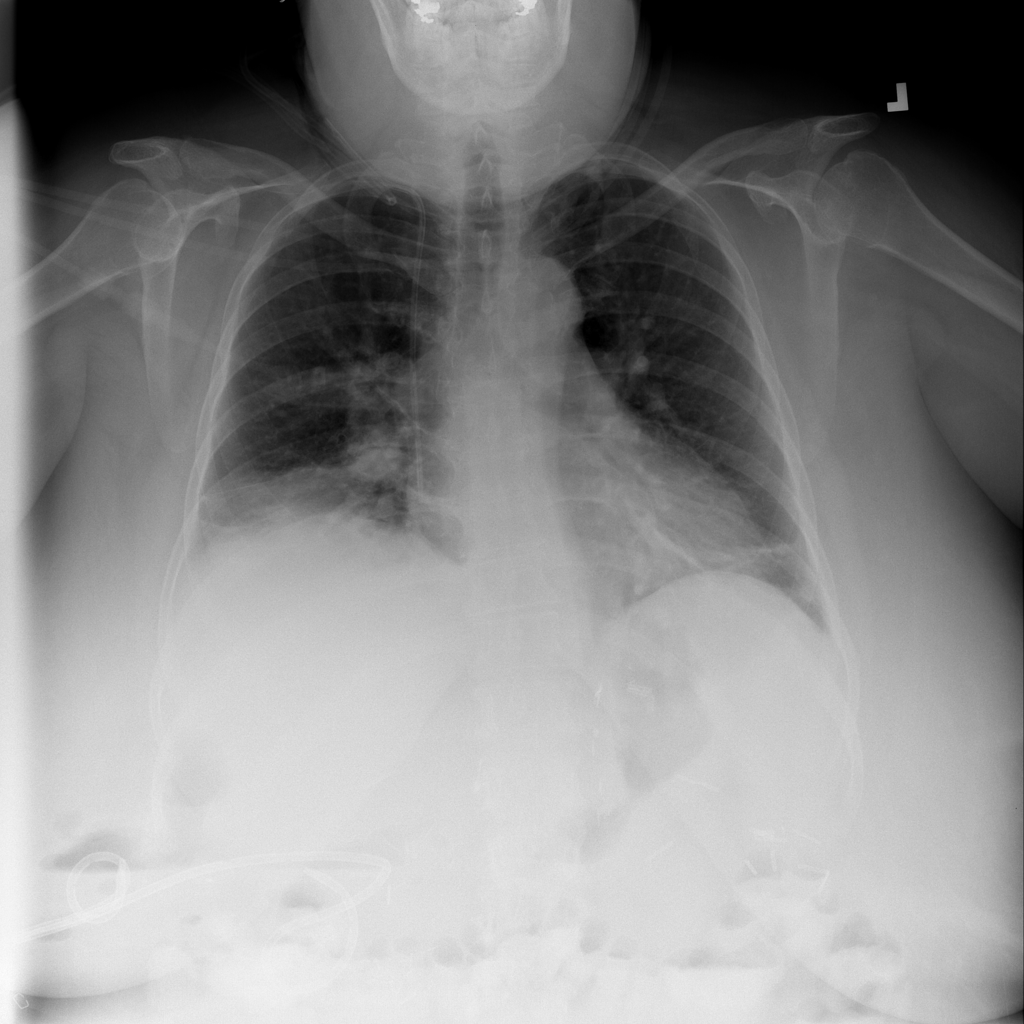

PAT-C0E5 · IMG-015Pneumonia

PAT-C0E5 · IMG-015

AP